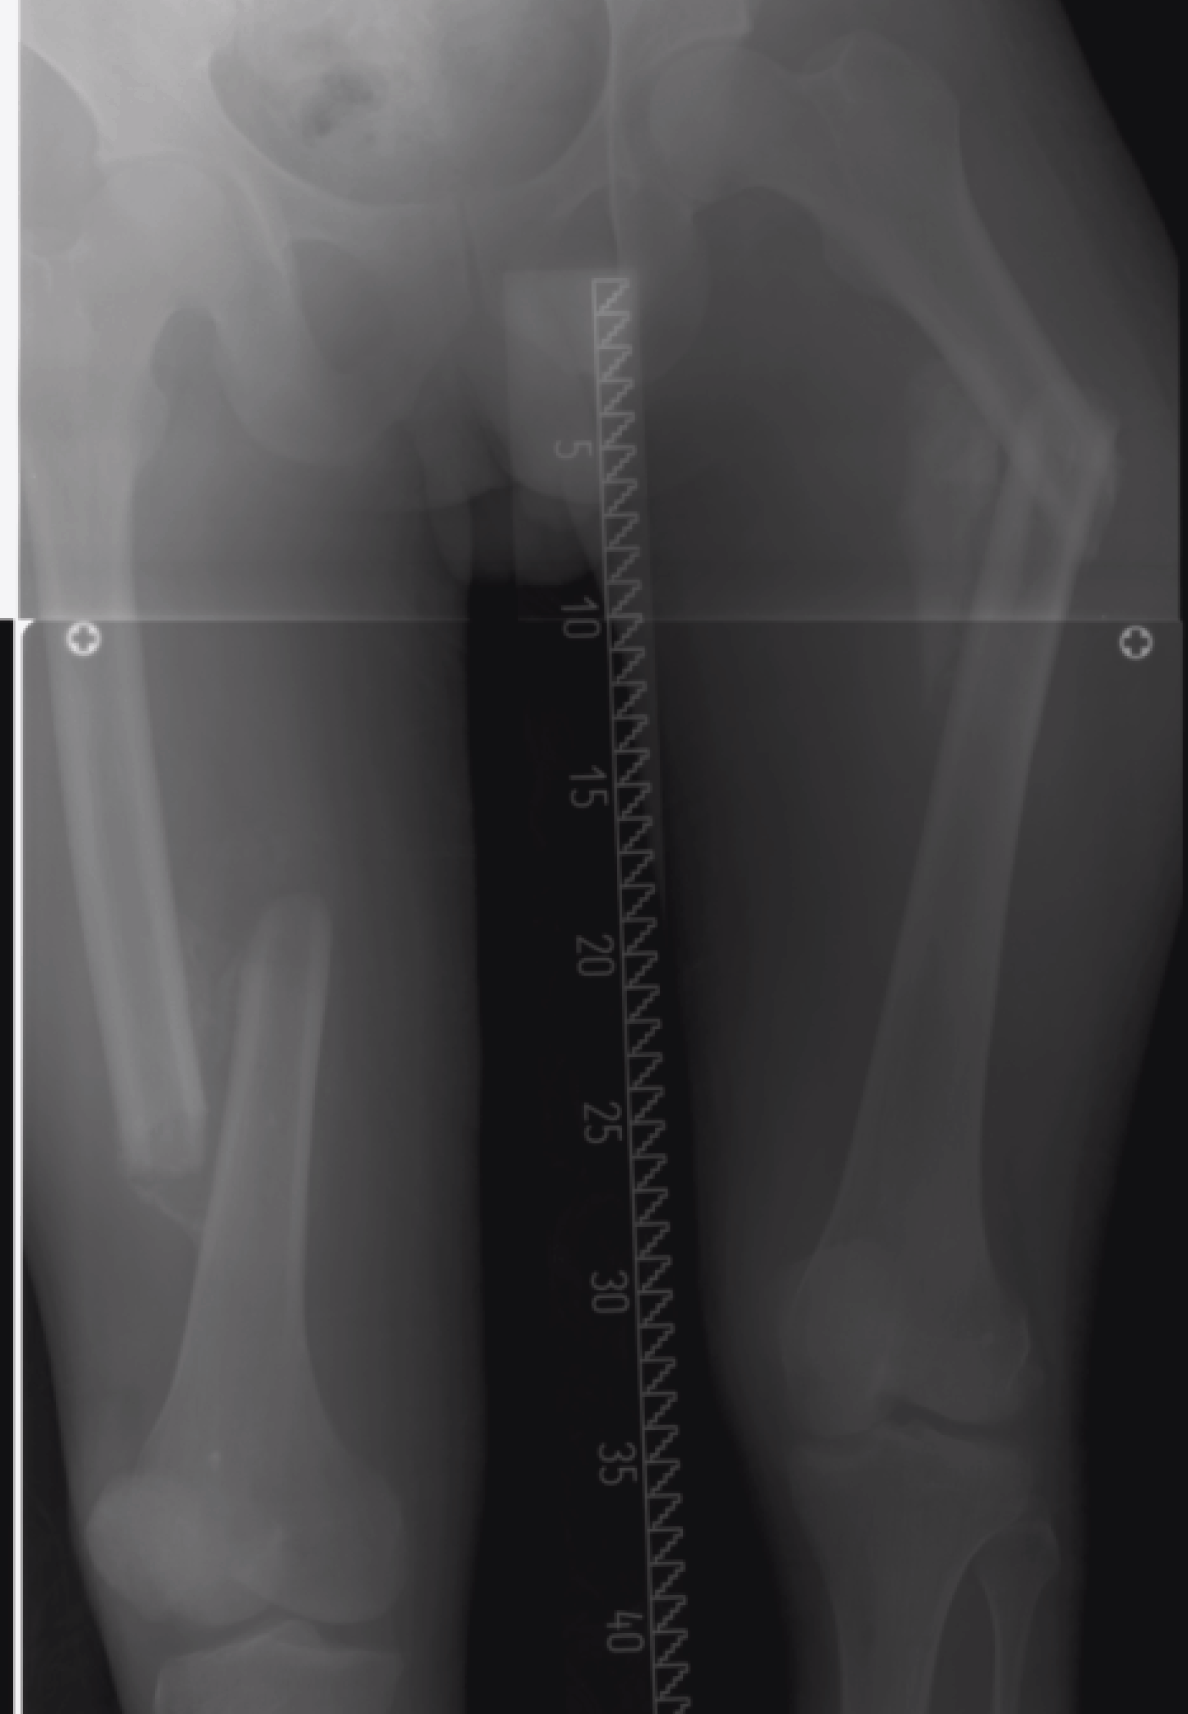

Definitive management for the bilateral femur racture still cannot be carried out in view of thyroid storm. Patient was resistant for the thyroid storm treatment, where it took almost one month under medical treatment to recover. During this period, as he was immobile, he developed 1st degree sacral sore which was treated with daily dressing and two hourly turning. Otherwise, there was no other complication occur related to prolong immobilization. Latest radiographs of bilateral femur showed huge callus formation with malunion of left femur. (Figure 3) Clinical evaluation showed shortening of the left lower limb around 5 cm. Clinically, fracture already united with minimal tenderness on movement.

Figure 3: Malunion bilateral femur fracture.